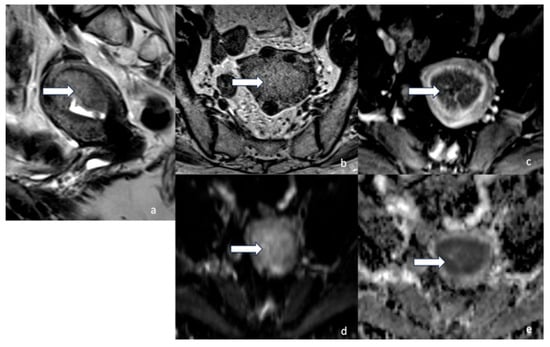

5.3. Magnetic Resonance Imaging (MRI)

- Maheshwari, E.; Nougaret, S.; Stein, E.B.; Rauch, G.M.; Hwang, K.-P.; Stafford, R.J.; Klopp, A.H.; Soliman, P.T.; Maturen, K.E.; Rockall, A.G.; et al. Update on MRI in Evaluation and Treatment of Endometrial Cancer. RadioGraphics 2022, 42, 2112–2130. [Google Scholar] [CrossRef] [PubMed]

- Rechichi, G.; Galimberti, S.; Signorelli, M.; Franzesi, C.T.; Perego, P.; Valsecchi, M.G.; Sironi, S. Endometrial Cancer: Correlation of Apparent Diffusion Coefficient With Tumor Grade, Depth of Myometrial Invasion, and Presence of Lymph Node Metastases. Am. J. Roentgenol. 2011, 197, 256–262. [Google Scholar] [CrossRef]

- Keles, D.K.; Evrimler, S.; Merd, N.; Erdemoglu, E. Endometrial cancer: The role of MRI quantitative assessment in preoperative staging and risk stratification. Acta Radiol. 2022, 63, 1126–1133. [Google Scholar] [CrossRef] [PubMed]

- Nougaret, S.; Reinhold, C.; Alsharif, S.S.; Addley, H.; Arceneau, J.; Molinari, N.; Guiu, B.; Sala, E. Endometrial Cancer: Combined MR Volumetry and Diffusion-weighted Imaging for Assessment of Myometrial and Lymphovascular Invasion and Tumor Grade. Radiology 2015, 276, 797–808. [Google Scholar] [CrossRef]

- Nougaret, S.; Horta, M.; Sala, E.; Lakhman, Y.; Thomassin-Naggara, I.; Kido, A.; Masselli, G.; Bharwani, N.; Sadowski, E.; Ertmer, A.; et al. Endometrial Cancer MRI staging: Updated Guidelines of the European Society of Urogenital Radiology. Eur. Radiol. 2019, 29, 792–805. [Google Scholar] [CrossRef]